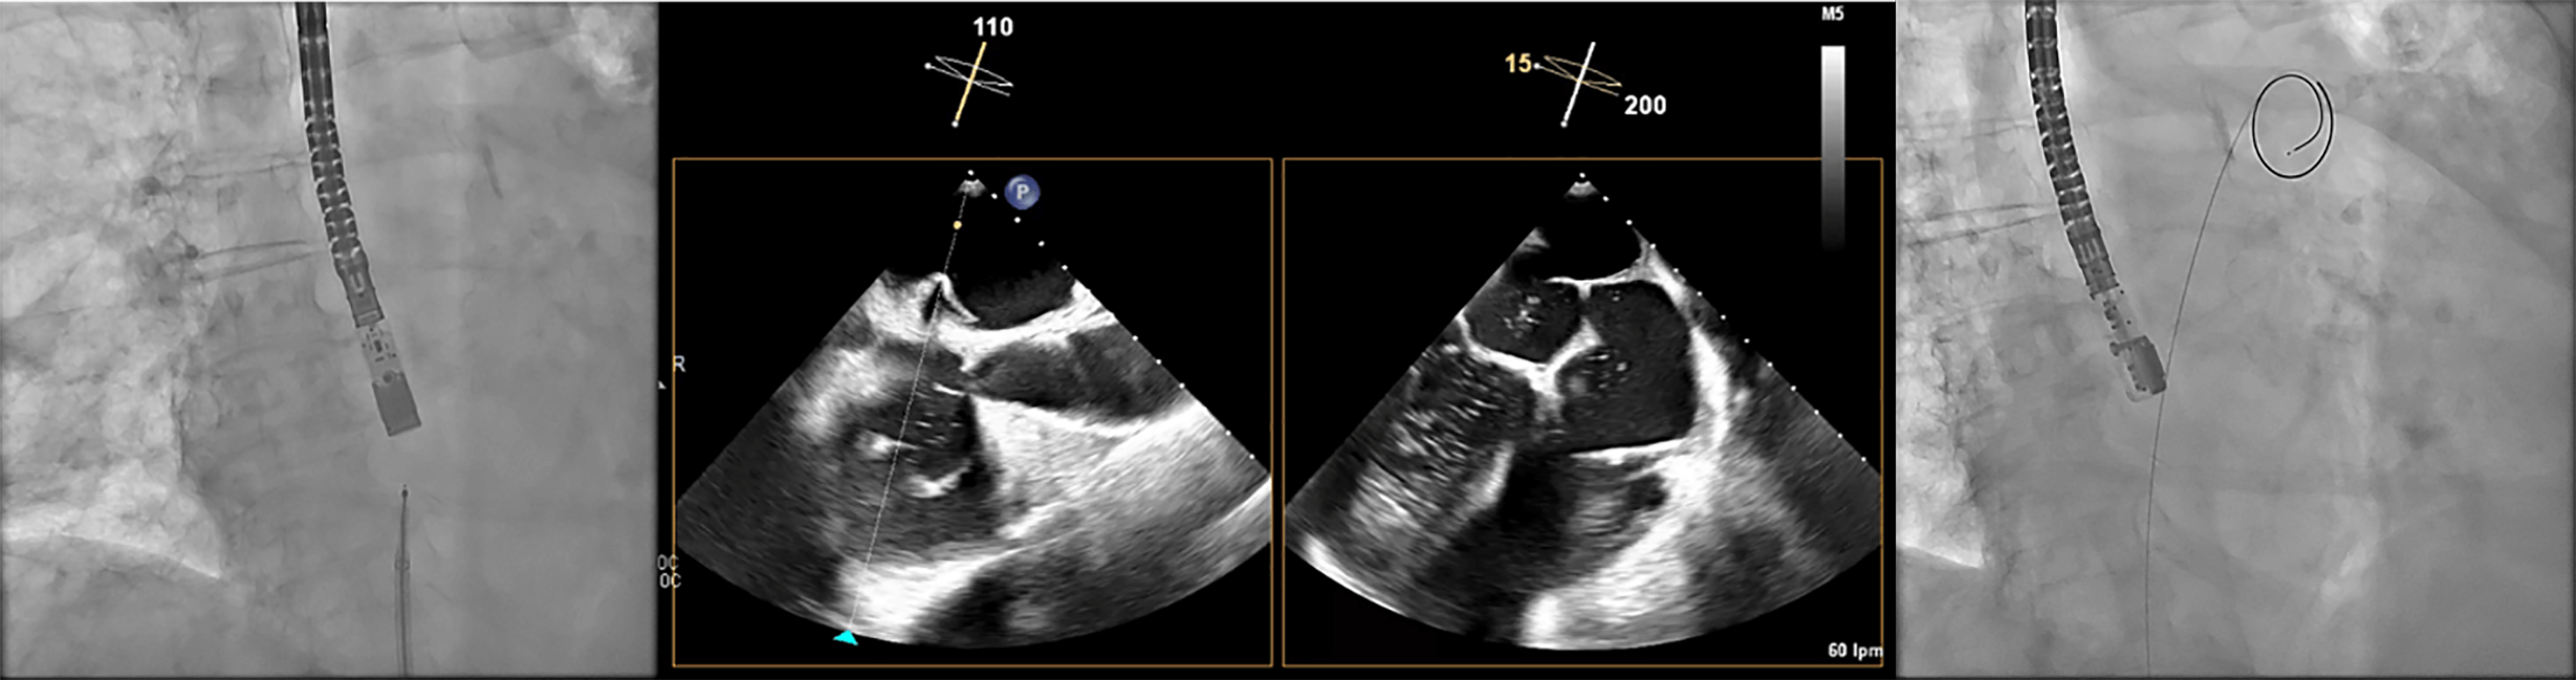

One of the most critical steps in LAAC is the TSP. The LAA is typically located in the anterosuperior portion of the LA and directed laterally and anteriorly. Consequently, an inferoposterior puncture within the fossa ovalis provides the most favorable trajectory for aligning the access sheath along the LAA’s long axis, thereby facilitating precise device positioning (Fig. 5) [15]. In cases where the LAA includes an additional, very anteriorly oriented lobe, a mid-fossa puncture—rather than an excessively posterior one—may provide better alignment with the target segment (Fig. 6). A TSP is traditionally performed using a Brockenbrough needle in combination with a transseptal sheath (Abbott, Abbott Park, IL, USA). We prefer the VersaCross® Transseptal System (Baylis Medical, part of Boston Scientific Corporation, Marlborough, MA, USA), which integrates a radiofrequency (RF) puncture system with an exchange-ready pigtail wire. This design facilitates both safe LA access and efficient navigation during the procedure. The pigtail wire, positioned within the transseptal sheath, is connected to an RF generator. Once the sheath tents the fossa ovalis appropriately, RF energy is applied, allowing the guidewire to cross into the LA, where it safely coils, thereby minimizing the risk of atrial wall injury (Fig. 7).

Fig. 5.

Transesophageal echocardiography (TEE) shows the tenting effect of the transseptal needle on the fossa ovalis in an inferior (left) and posterior (right) position.

Transseptal puncture (TSP) using the VersaCross system. The Versacross wire, within its sheath, is seen in contact with the interatrial septum under fluoroscopy (left). Transesophageal echocardiography (TEE) reveals tenting at the level of fossa ovalis and the wire crossing into the left atrium (middle), where it immediately assumes a pigtail shape (right), providing a safe means of crossing the septum.

Immediately after a successful TSP, additional unfractionated heparin is given to reach a total dose of 100 U/kg. Then, the pigtail-shaped guidewire, which offers high support, is advanced and coiled within the LSPV by gentle clockwise rotation. This position allows smooth advancement of the VersaCross sheath into the LA for septal dilation. We maintain the same wire in the LSPV for the subsequent advancement of the dedicated LAAC delivery sheath (Fig. 8). Once the dedicated sheath reaches the LA and is positioned near the LSPV, a pigtail catheter is advanced over the VersaCross wire into the LA, after which the wire is withdrawn. With a gentle counterclockwise rotation of the assembly, the pigtail is directed and positioned within the LAA. At this stage, LAA angiography is performed in two standard projections: right anterior oblique (RAO) 30°/cranial 20° and RAO 30°/caudal 20°, which correspond to the 45° and 135° TEE views, respectively (Table 3). Guided primarily by TEE—and secondarily by angiography—the device size is selected following precise evaluation of the landing zone and theoretical device positioning within the LAA. Although several occlusion devices are currently available (Table 4), we provide a detailed procedural overview of two of the most widely used LAAC systems worldwide.

Fig. 8.

Advancement of the sheath over the VersaCross wire. The Versacross wire is positioned in the left superior pulmonary vein (LSPV), as seen in the fluoroscopy image (upper left) and confirmed by transesophageal echocardiography (TEE) (upper right). The dedicated sheath for left atrial appendage closure (LAAC) device was advanced successfully over the same wire up to the LSPV, as visualized by TEE (bottom image).